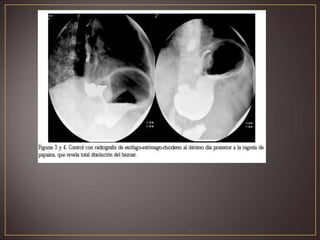

Radiografía simple de abdomen. Radiografíacontrastada. Endoscopía Alta confirma el diagnóstico. observación de las deposiciones en las que hayan sido expulsados restos del material ingerido. por la observación de zonas de alopecia.

Extracción endoscópica depequeños bezoares gástricos Enzimas como la papaína(disuelve proteínas) ó acetilcisteína (disuelve el moco) asociadas a cisapride, moperidona, metoclopramida en los pacientes con retraso en la evacuación gástrica. los bezoares pueden mostrar obstrucciones intestinales , intermedias o bajas y necesitar tratamiento quirúrgico.